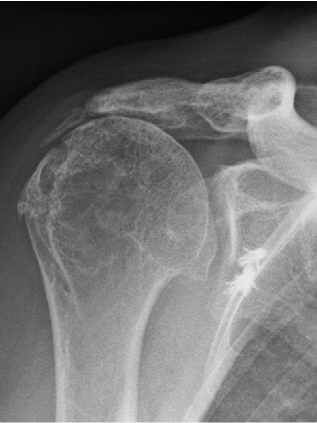

Das Fallbeispiel zeigt ein Röntgenbild mit Arthrose von Kopf und Pfanne mit aufgebrauchtem Gelenkspalt und ein postoperatives Röntgenbild nach 3 Jahren mit eingebrachter TEP (Kopf und Pfanne wurden ersetzt). Da die Gelenkpfanne aus Polyethylen ist, kann man sie auf dem Röntgenbild nicht so genau sehen wie die Kopfprothese.